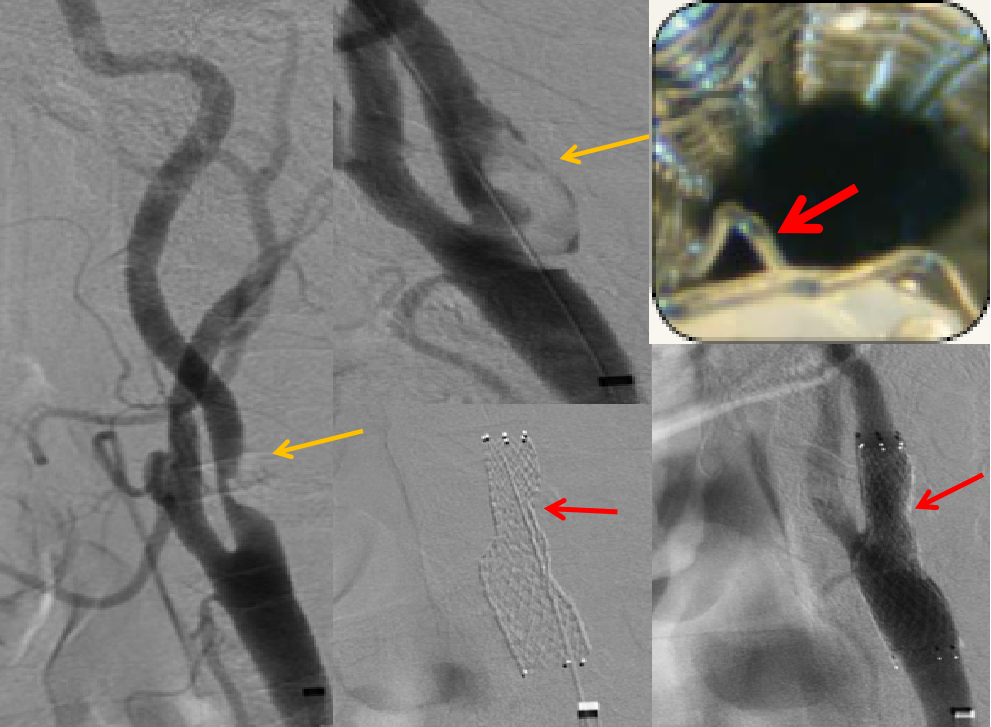

案例3

这是一个取支架的病例,支架内再狭窄,支架膨胀不全。贴近颈内动脉远端的支架里很光滑,从最后一幅图看,最狭窄处内膜增生严重。这是因为局部涡流形成,导致支架内再狭窄。